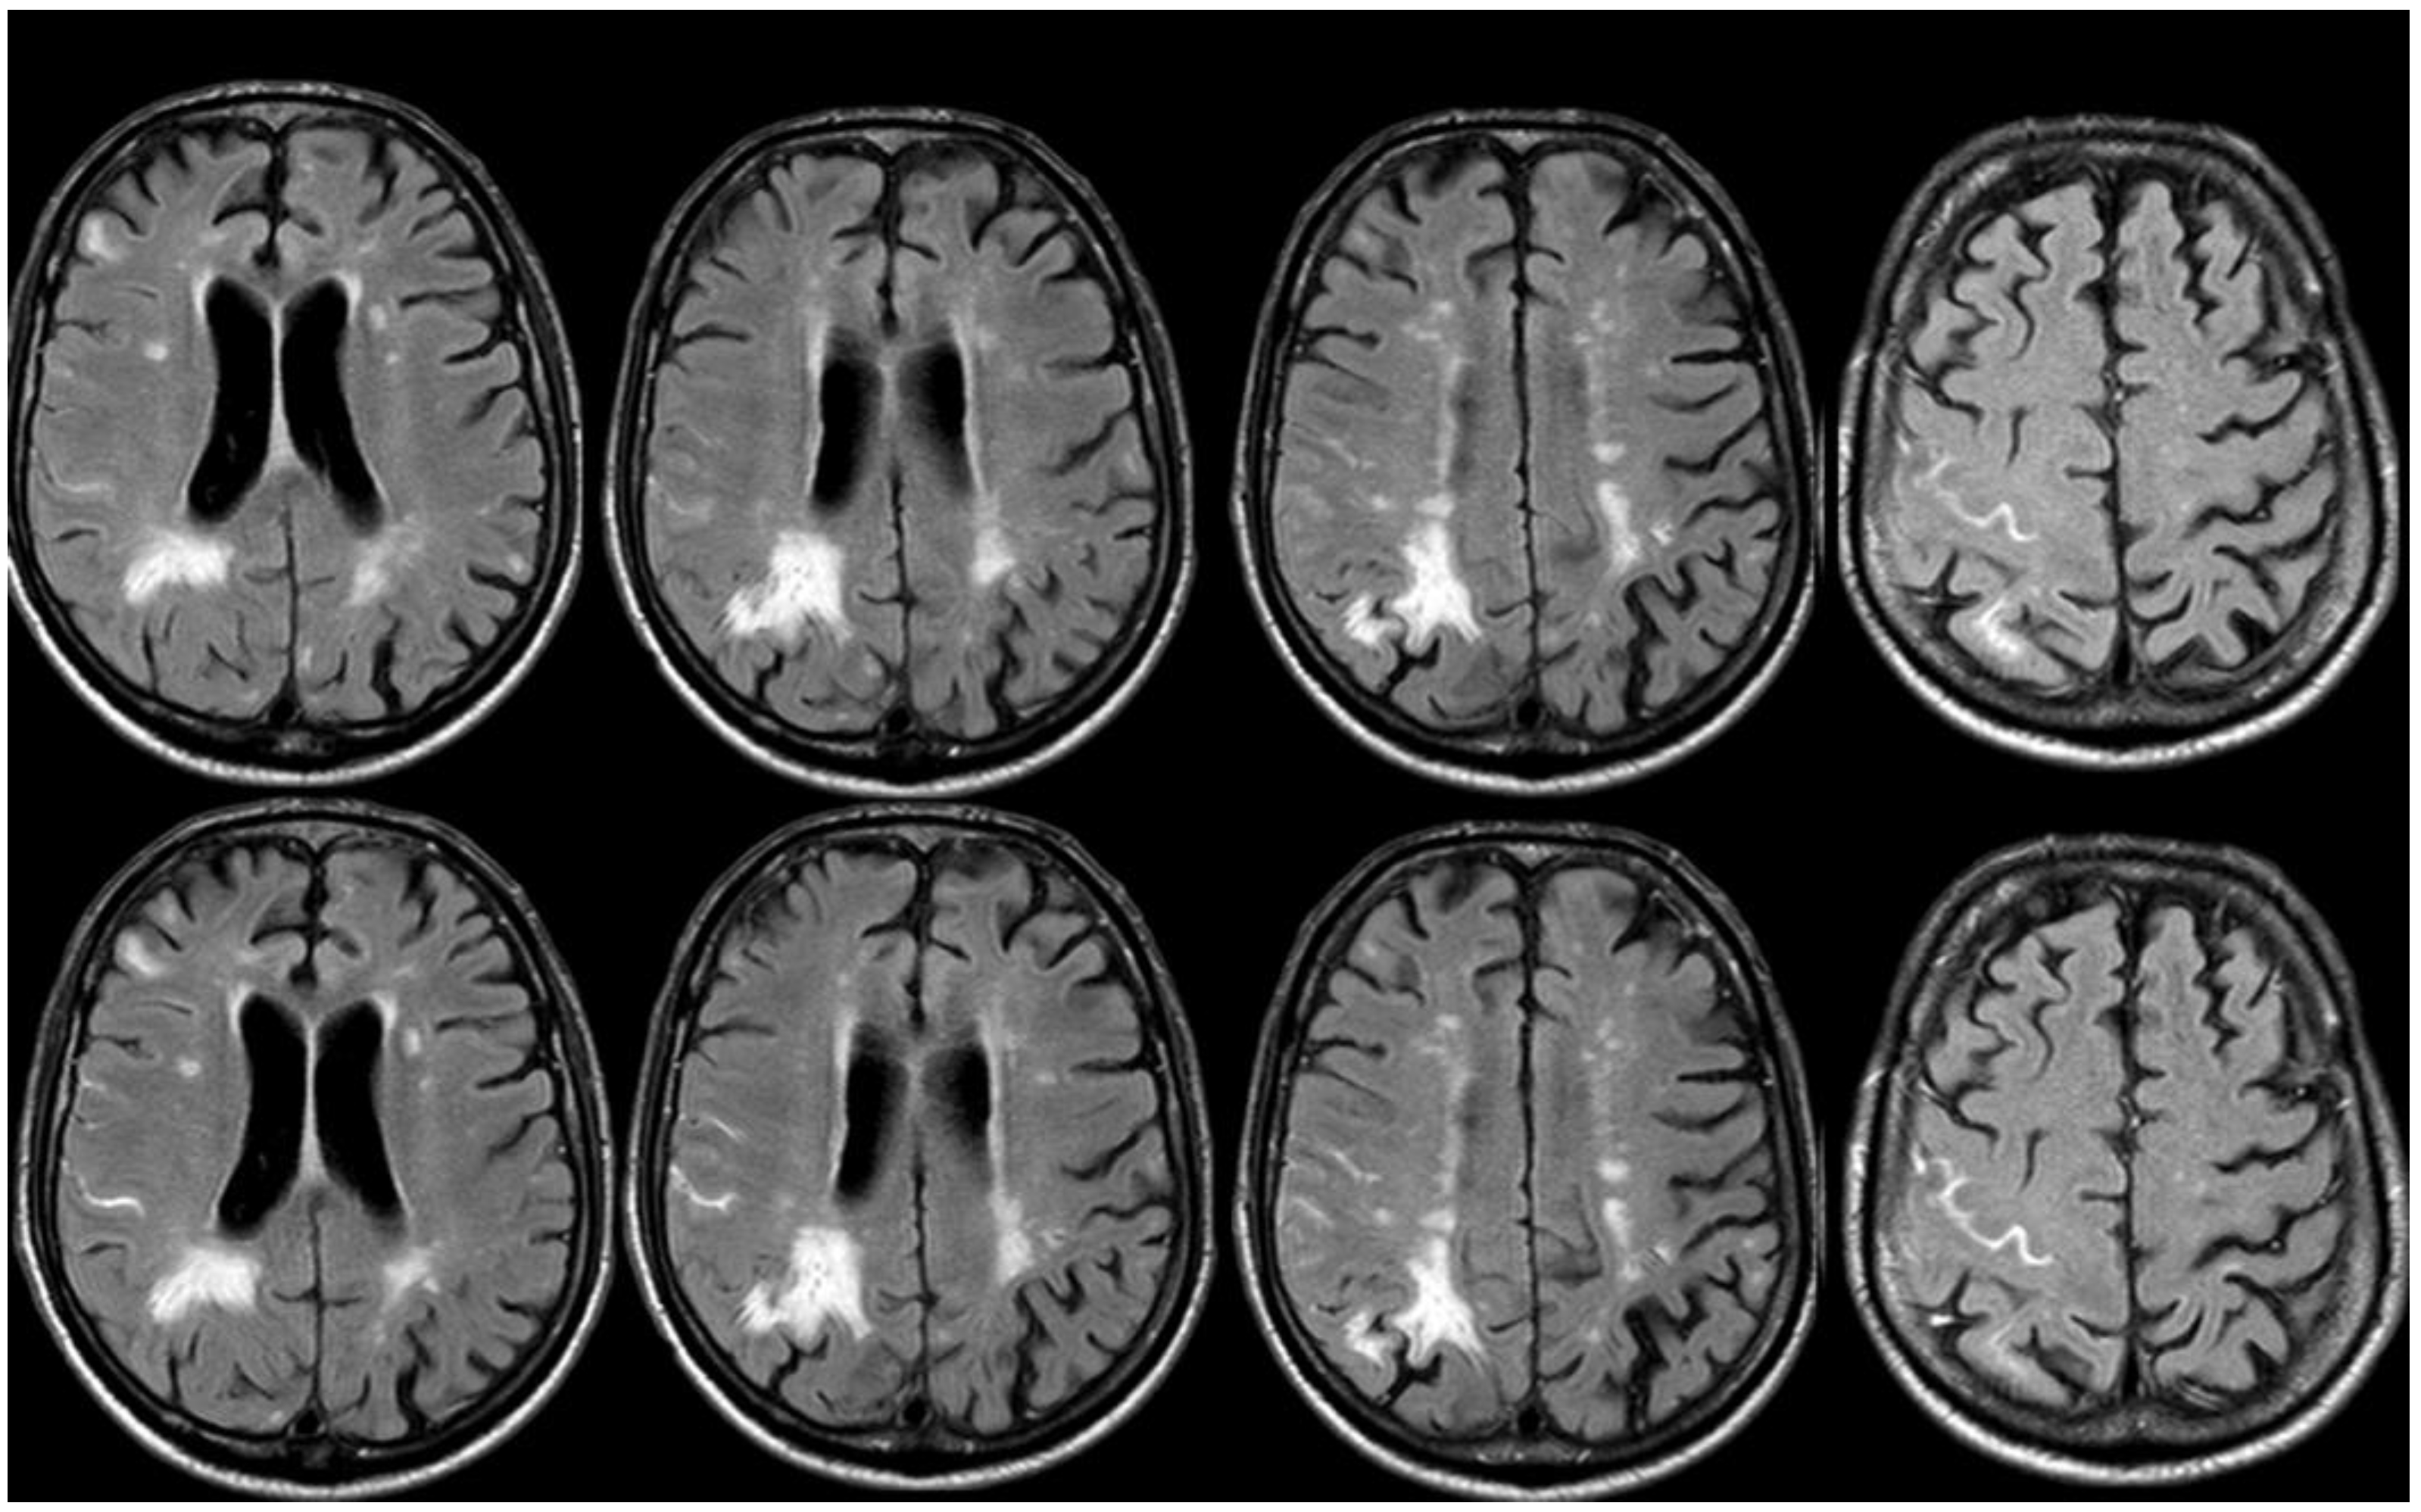

8. April 2018: Third Recurrent CAA-Related Inflammation

9. Additional Information and Discussion: How This Case Helps to Better Understand CAA